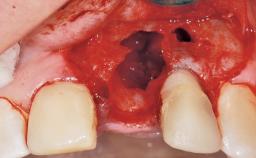

Immediate Flapless Placement of an Implant in a Maxillary Left Central Incisor Site

A 42-year-old female patient was referred to our clinic at the School of Dentistry of the University of São Paulo in November 2004, presenting a deficient restoration in the upper left central incisor. The clinical examination revealed no gingival retraction or any signs of gingival inflammation and, therefore, previous periodontal treatment was not considered. The patient presented a high lip line at full smile and a thin tissue biotype. This combination characterized a high-risk situation from an anatomic point of view, which required careful preoperative planning and cautious surgical execution.

Soft Tissue Anatomy Intact Defective

Socket Integrity Sufficient, with intact bone walls

Bone Volume Sufficient, with intact walls

Esthetic Risk Medium